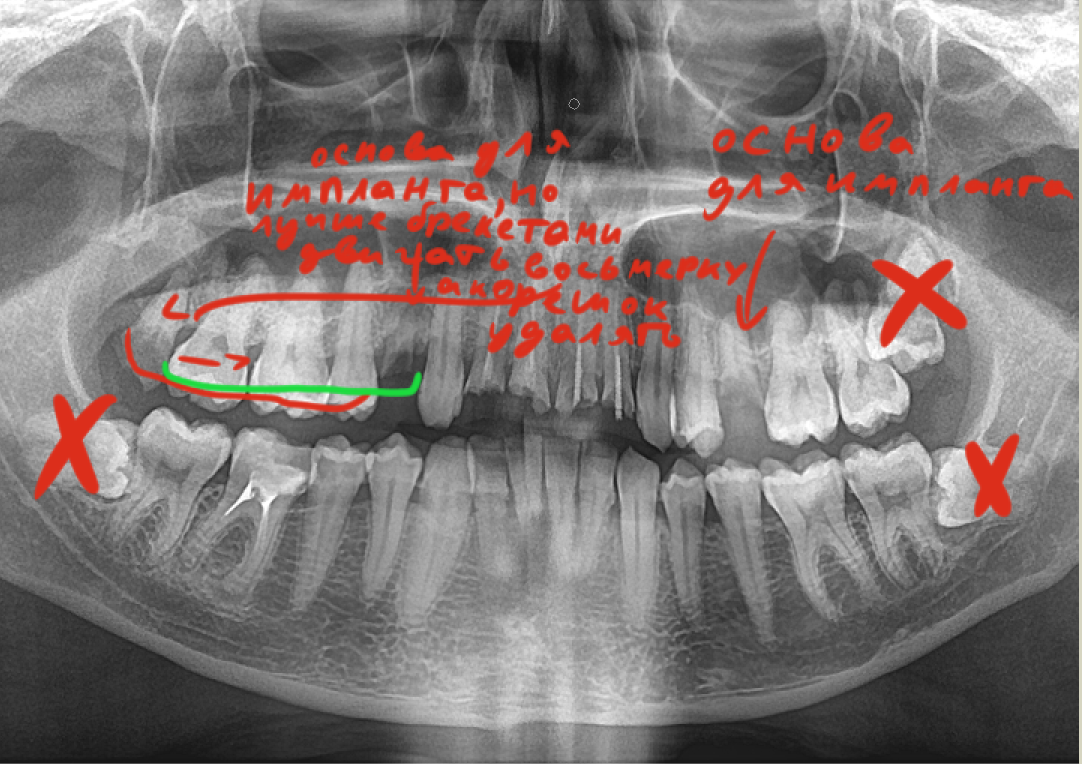

>>1634947

>Как профиль лица меняется после удаления восьмерок

Удаляли две, одну сверху другую снизу. Никаких изменений.